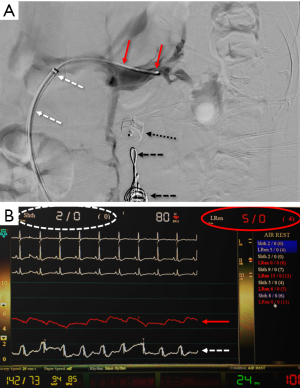

A comparison of DUS (LRV systolic velocity ratios) to CT (vein diameter ratios) demonstrates higher sensitivity and specificity of DUS findings (sensitivity of 80% vs. 69%; specificity of 94% vs. 89%, respectively) (34,36). However, invasive testing is frequently pursued for definitive diagnosis, as therapy could require invasive surgery. Venography with direct pressure measurements (Figure 7) (17), with or without intravascular ultrasound (IVUS), is considered the “gold standard” for diagnosis. However, even studies evaluating these methods utilized cystoscopy to confirm isolated left-sided hematuria (2). An elevated pressure gradient between the LRV and the IVC (≥3 mmHg) is the standard reference point by which venous hypertension is diagnosed (43). However, it should be noted that some patients may be symptomatic with “compensated” NCS, where compensatory flow through collaterals is large enough that only a borderline renocaval pressure gradient exists (2).